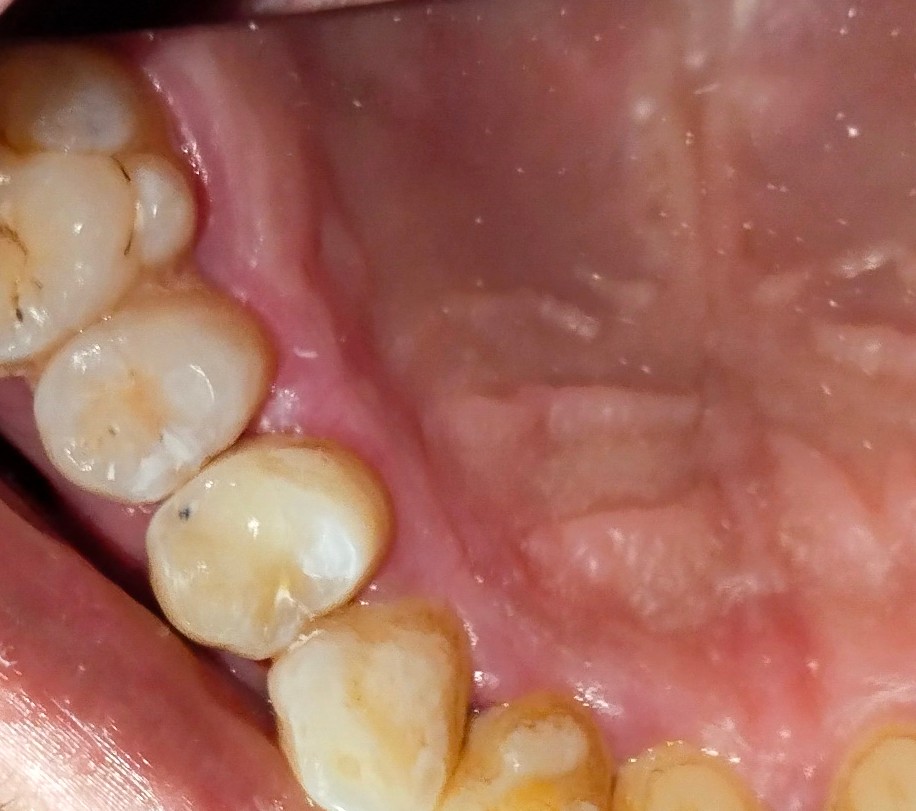

Utilizing rotary endodontics, we performed the RCT on Rahim’s upper right first premolar, known for often having two canals. In Rahim’s case, we confirmed the presence of two canals—the buccal canal measuring 21mm and the palatal canal measuring 22mm. Despite the complexity, the advanced techniques ensured precise treatment and Rahim’s comfort.

Following the successful Root canal treatment, Rahim received essential post-operative instructions. He was advised not to bite on the same side for a week to allow for healing. Afterward, he could gradually introduce soft foods on that side. Additionally, Rahim was recommended to get a crown after two weeks to further protect and strengthen the treated tooth.

It’s crucial to note that the success of Root canal treatment depends significantly on proper technique. Using an X-ray and sensor from Eighteeth for working length confirmation of root canals, we ensured a precise understanding of the working length. In many failed RCT cases, under-obturation is observed, highlighting the importance of thoroughly cleaning the canal to the apex and then well-obturating it for a successful outcome.